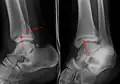

AP manual stress view showing a deltoid ligament tear